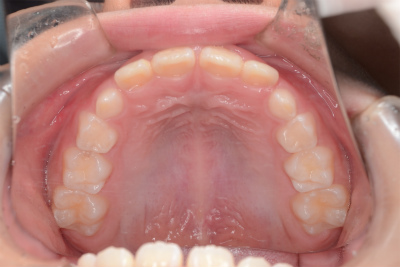

小学3年生